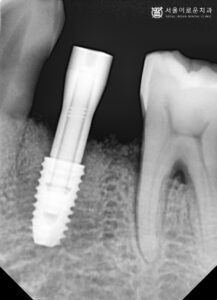

위에 x-ray 사진은 임플란트 상부에

custom abutment

( 커스텀 맞춤형 어벗트먼트)를

체결한 뒤 안정적으로 연결이 되었는지

확인하기 위해 촬영한 것입니다.

custom abutment는

사이즈가 정해진 기성 어벗트먼트와 달리,

맞춤형 제작으로 환.자분의

구강환경에 최적화되어 제작된 것으로

안정성과 편안한 느낌을 줍니다.